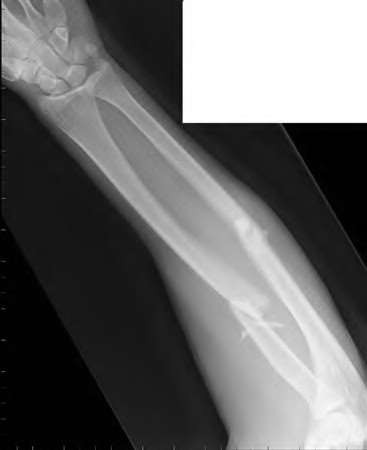

Question 6:

A 22-year-old male falls onto an outstretched hand and sustains a displaced fracture through the proximal pole of the scaphoid. Avascular necrosis of the proximal pole is highly likely due to the disruption of its primary vascular supply. Which vessel provides this critical retrograde perfusion?

Correct Answer: Dorsal carpal branch of the radial artery

Explanation:

The primary blood supply to the scaphoid is from the dorsal carpal branch of the radial artery, which enters the dorsal ridge of the scaphoid at the waist and courses proximally. This retrograde blood flow makes proximal pole fractures highly susceptible to avascular necrosis and nonunion. The superficial palmar branch provides a minor supply (about 20%) to the distal pole.